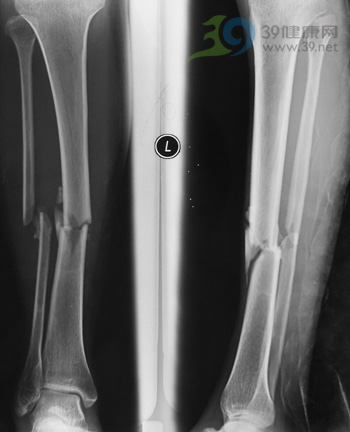

一、骨折的判断

1.剧烈的疼痛:由于骨折处的尖端刺伤周围组织的血管、神经,活动时骨折局部剧烈疼痛,并有明显压痛、肿胀。

2..畸形:骨折部位在肌肉的作用下,形态改变,如成角、旋转、肢体缩短等。

3.骨摩擦音及骨摩擦感:骨折断端相互碰触时出现的声音和感觉。严禁有意去做此项检查。

4.功能障碍:骨的支撑、运动、保护等功能受到影响或完全丧失。